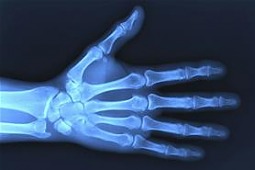

Prawidłowa struktura kości jest wypadkową aktywności dwóch typów komórek. Pierwsze to osteoblasty, tworzą one mineralne rusztowanie kości. Drugi typ to osteoklasty. Komórki te odpowiadają za resorpcję kości, czyli wchłaniają kości, są komórkami żernymi. Równowaga pomiędzy przeciwstawnymi aktywnościami tych dwóch typów komórek podlega regulacji przez hormony, neurotransmitery i cytokiny.

Jak wyjaśnia Urszula Kędzierska, główna cytokina prozapalna - czynnik martwicy nowotworów - wpływa stymulująco na aktywność osteoklastów i hamuje aktywność osteoblastów. Dlatego zmniejszenie gęstości mineralnej kości, prowadzące do osteoporozy jest częstym zjawiskiem towarzyszącym przewlekłym stanom

zapalnym.